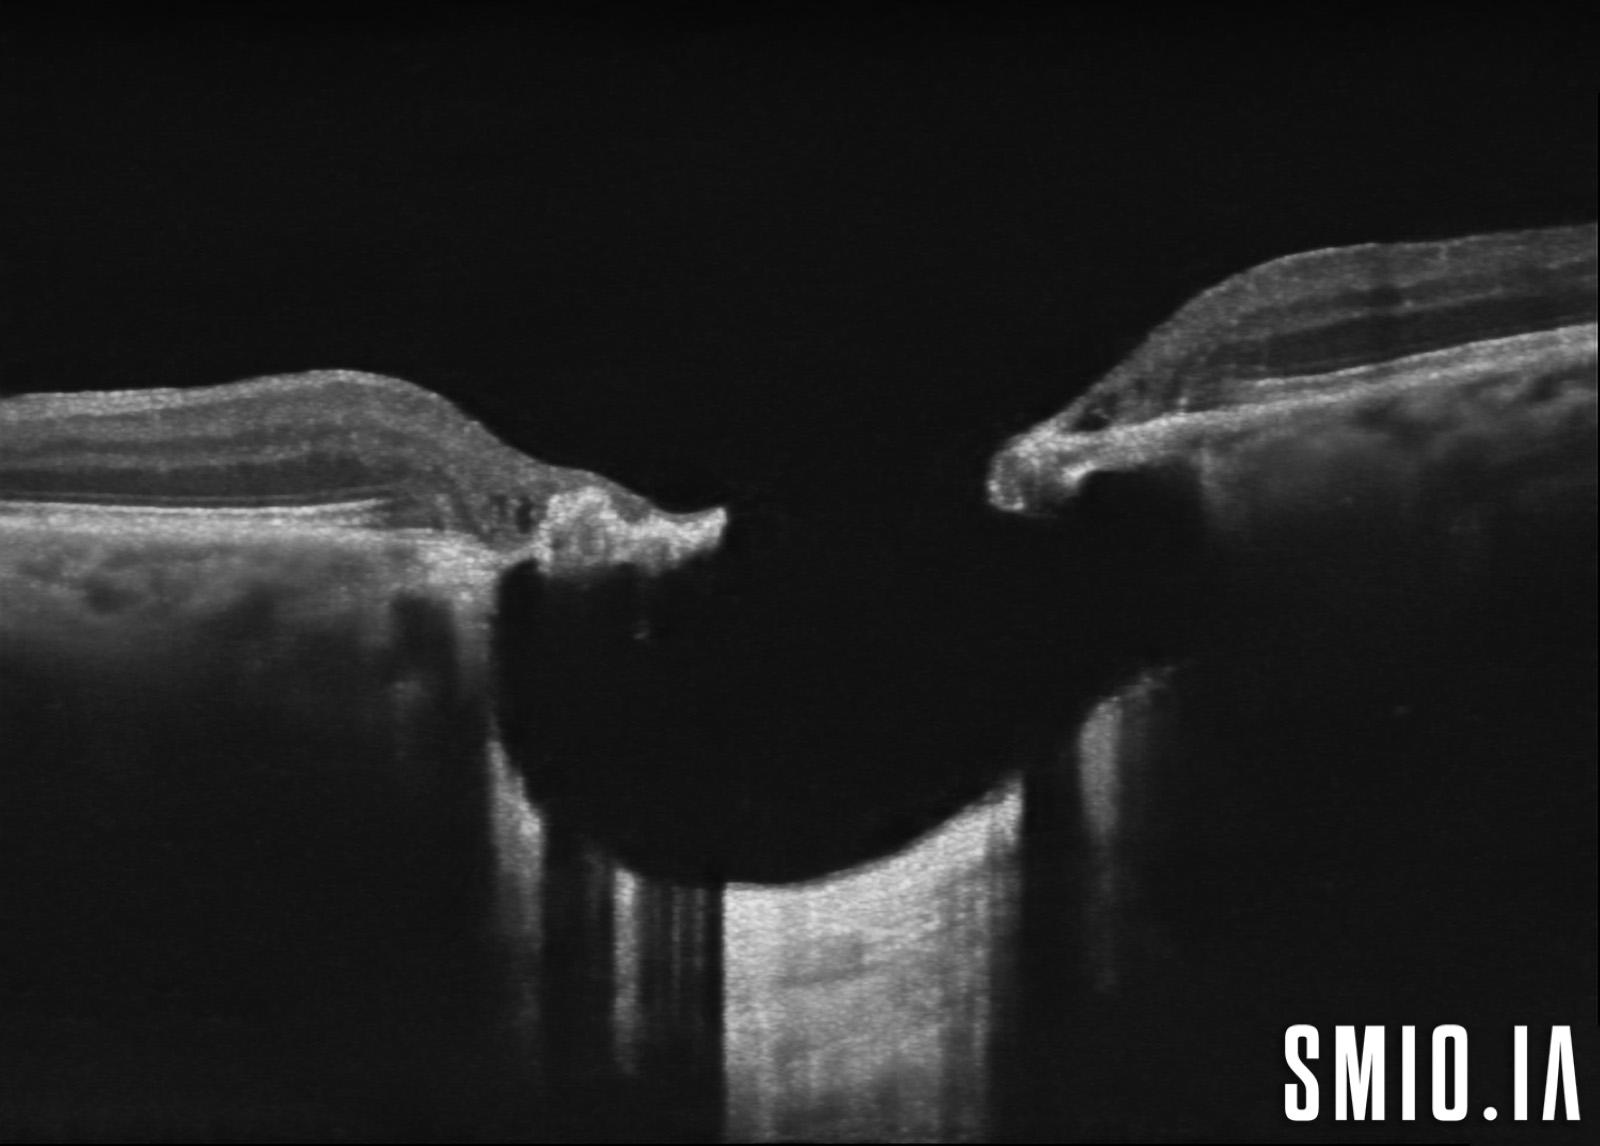

Description: L'image stéréo d'une cicatrice choriorétinienne de toxoplasmose oculaire congénitale avec l'OCT à travers la lésion a démontré une grande lésion choriorétinienne excavée de colobome avec une cavitation intrachoroïdienne